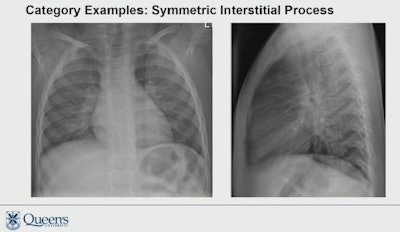

In this study, the researchers aimed to further establish the clinical importance of these associations. They reviewed 978 chest x-rays from children under 6 years old suspected of pneumonia who underwent imaging at two emergency departments between 2017 to 2020. Two pediatric radiologists interpreted the exams based on five patterns: normal, symmetric interstitial, asymmetric interstitial, asymmetric airspace, and mixed. Extensive clinical data were obtained, including the identified organism involved, and the researchers then correlated these with the chest x-ray patterns.

According to the readings, 42% of the chest x-rays were normal, 19% were interpreted as symmetric interstitial, 10% as asymmetric interstitial, 18% as asymmetric airspace, and 11% as mixed.

The analysis revealed that respiratory syncytial virus (RSV)-positive cases had normal interpretations in 20%, symmetric interstitial patterns in 46%, asymmetric interstitial patterns in 16%, and mixed pattern in 19% (p < 0.001). There were no known RSV cases demonstrating an asymmetric airspace pattern in the study, Kurtz noted.